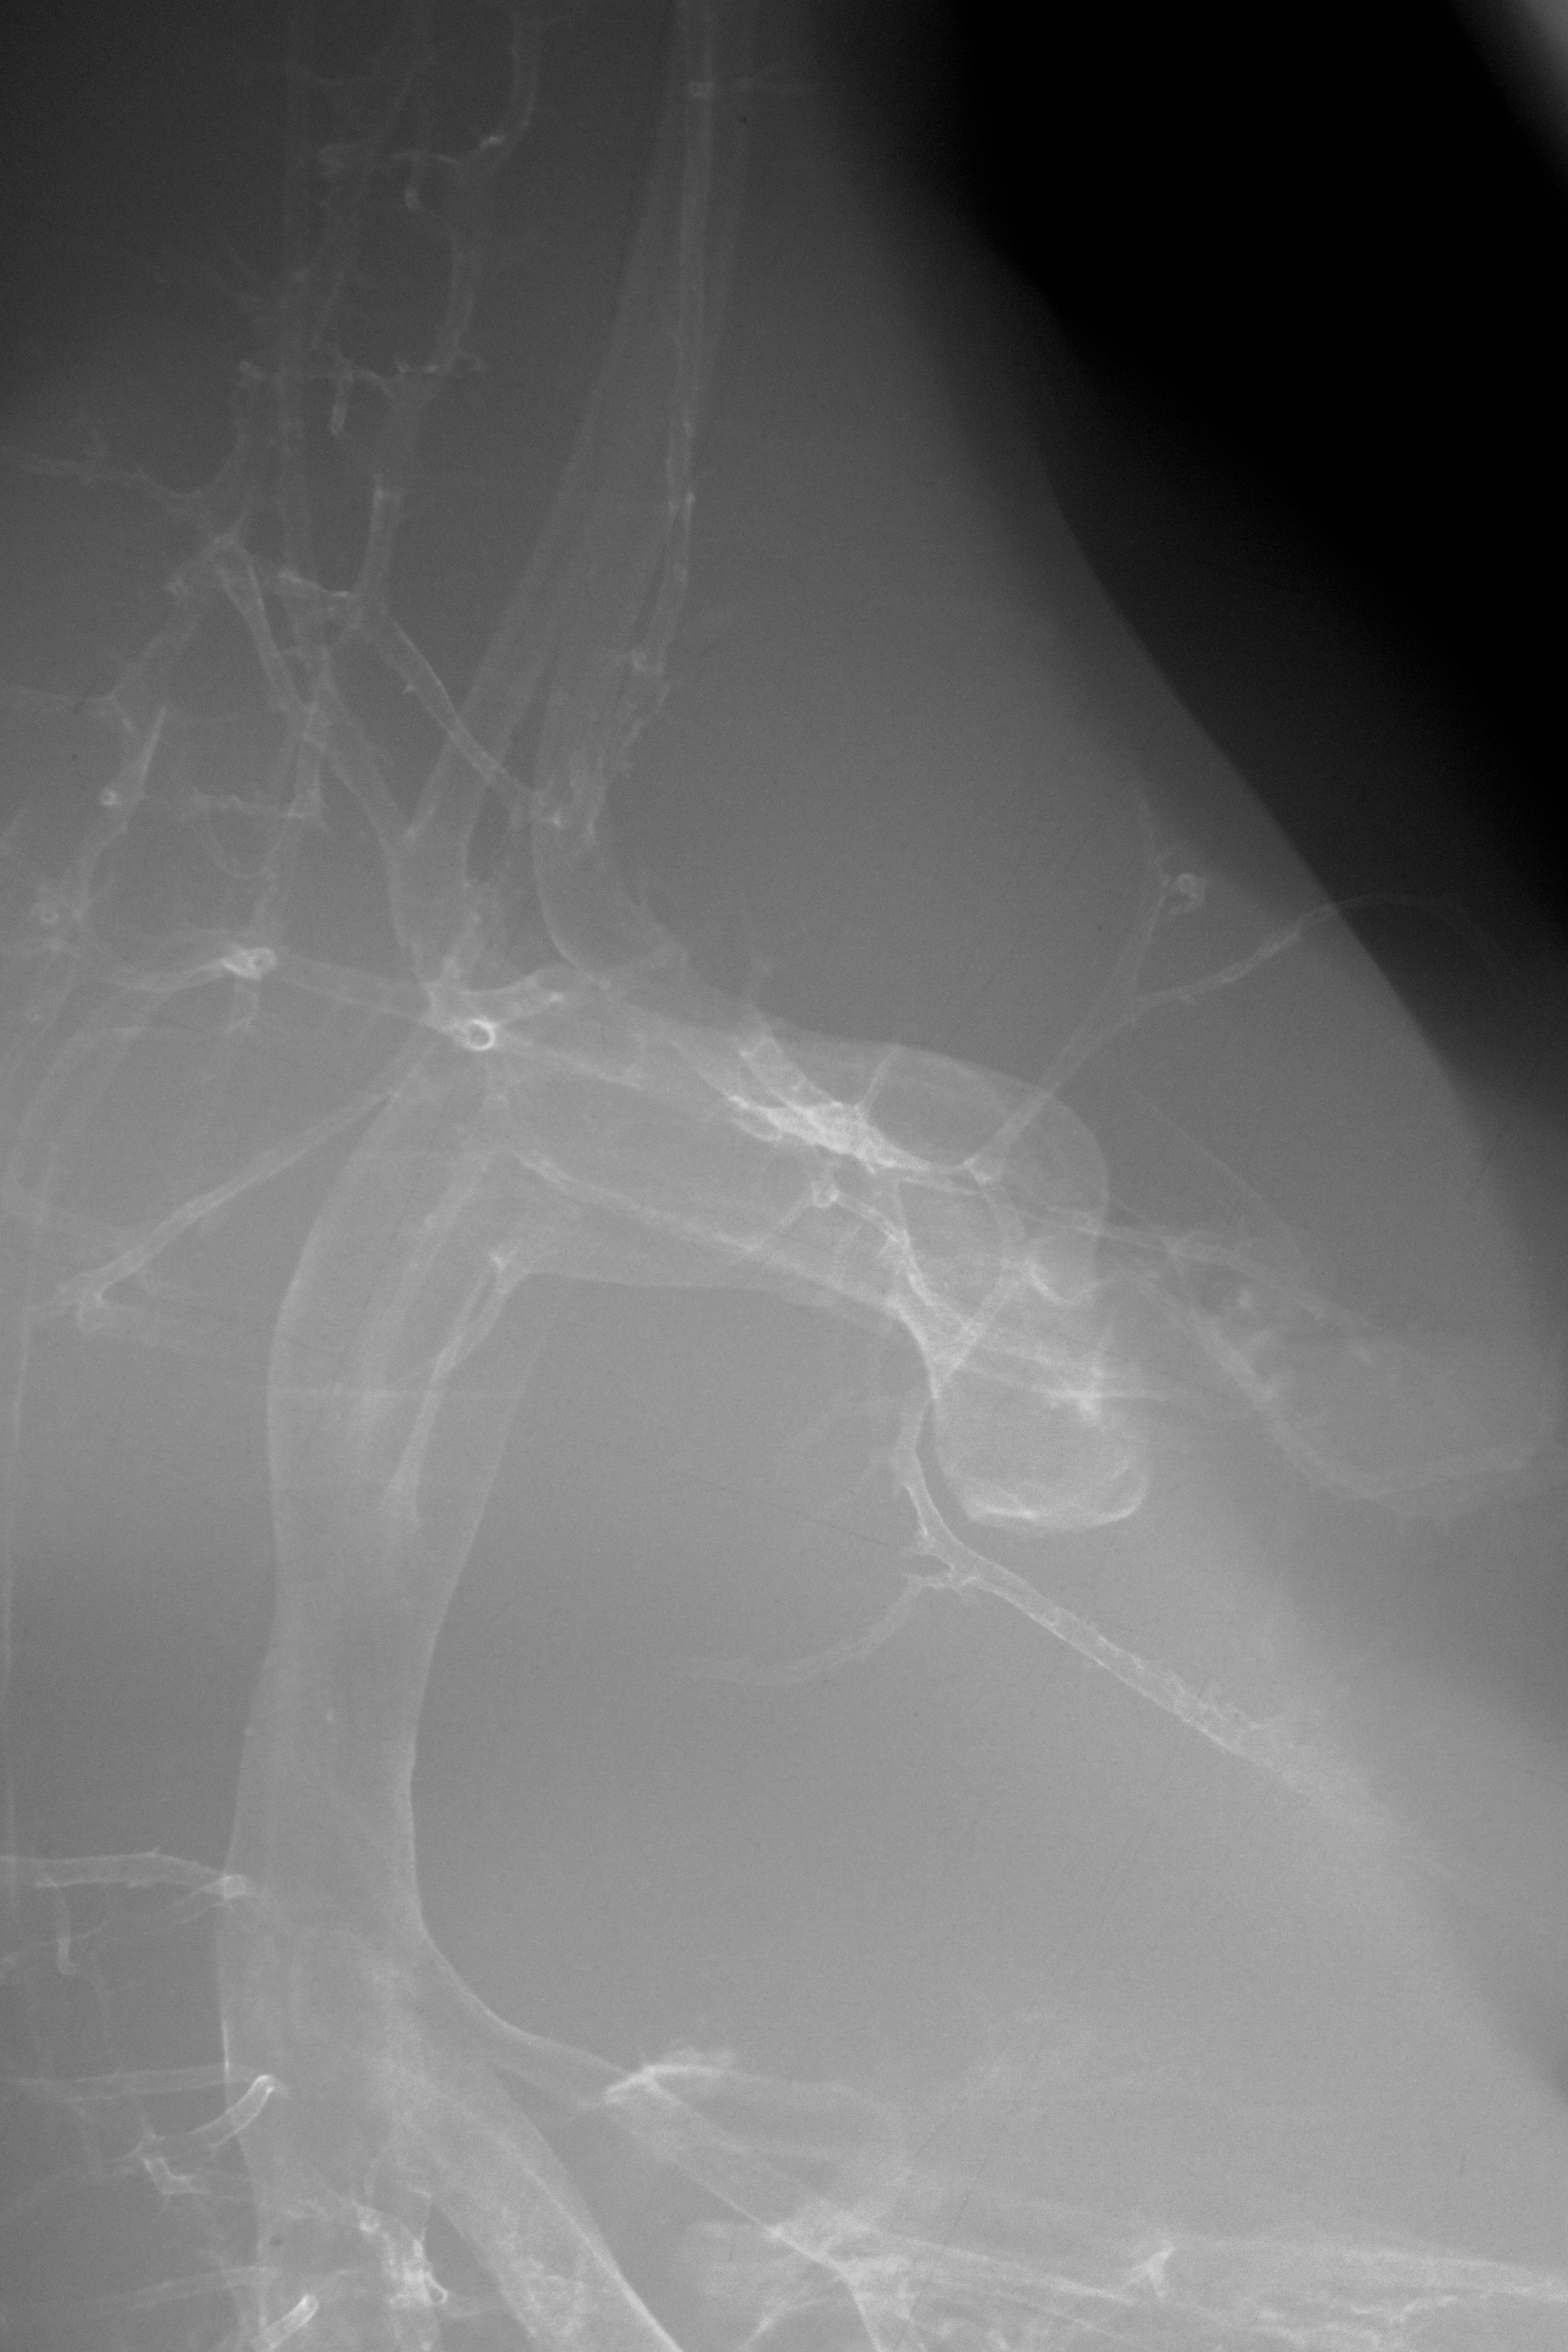

Chick Embryo Microangiography

Hamburger-Hamilton (HH) Stage 35 (approx. 8.5 - 9 days)

X-Ray Micrographs